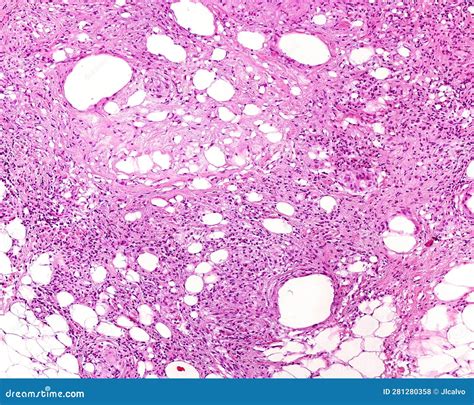

• Biopsy: In some cases, a biopsy may be performed to confirm the diagnosis. This involves removing a small sample of the affected tissue for laboratory analysis.